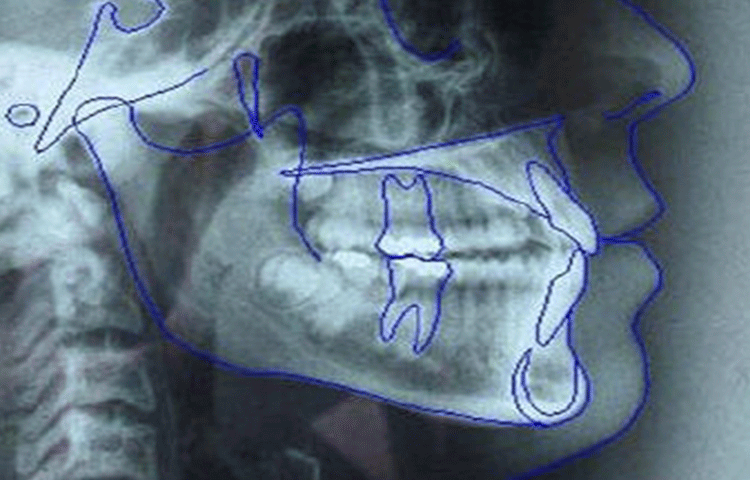

3. 資料取り

レントゲン、写真、歯の型取りなど、診断に必要な資料を取らせて頂きます。

4. 診断

取らせて頂いた資料をもとに診断し、治療の計画をいくつかご用意させて頂きます。